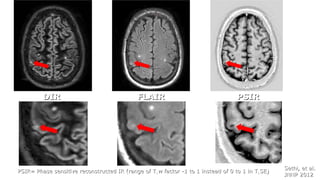

Sethi, et al.Sethi, et al.

JNNP 2012JNNP 2012

DIRDIR FLAIRFLAIR PSIRPSIR

PSIR= Phase sensitive reconstructed IR (range of TPSIR= Phase sensitive reconstructed IR (range of T11w factor -1 to 1 instead of 0 to 1 in Tw factor -1 to 1 instead of 0 to 1 in T11SE)SE)